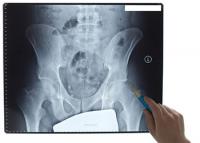

Investigadores de Valdecilla descubren nuevos identificadores de las fracturas en los huesos

Un grupo de investigadores del Hospital Universitario ‘Marqués de Valdecilla’ ha logrado identificar nuevos signos que permiten hallar la posibilidad de que se sufran más fracturas en los huesos.

La osteoporosis es una enfermedad esquelética caracterizada por una reducción de la densidad en la composición de los huesos y un aumento de la posibilidad de su rotura, en una dolencia que es heredable en proporciones altas.